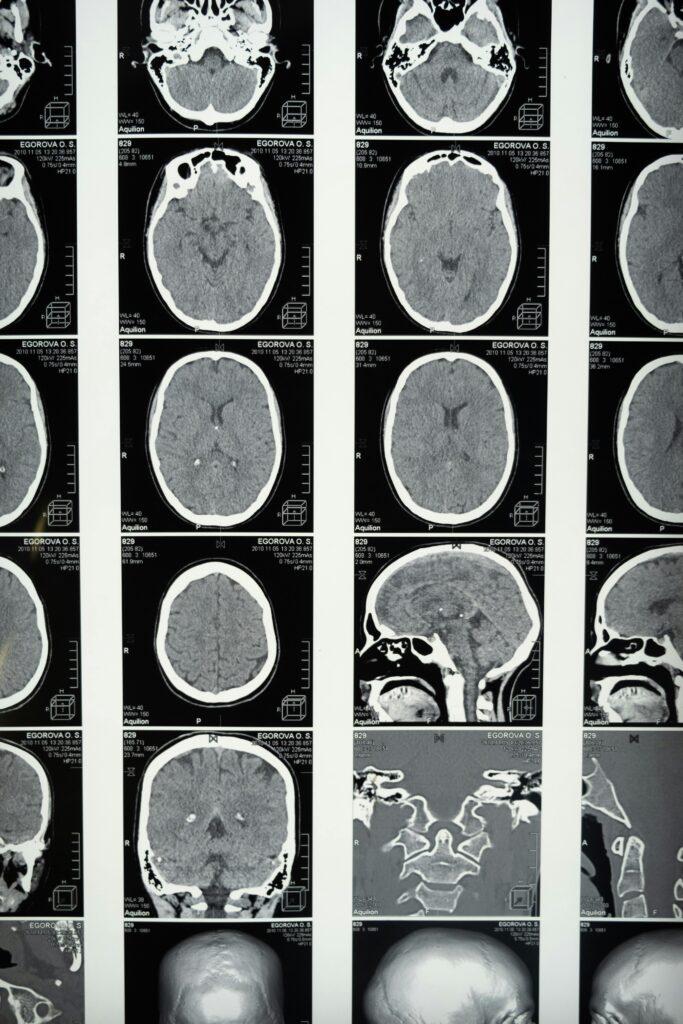

How to Help a Family Member Who Suffered a Traumatic Brain Injury in NYC